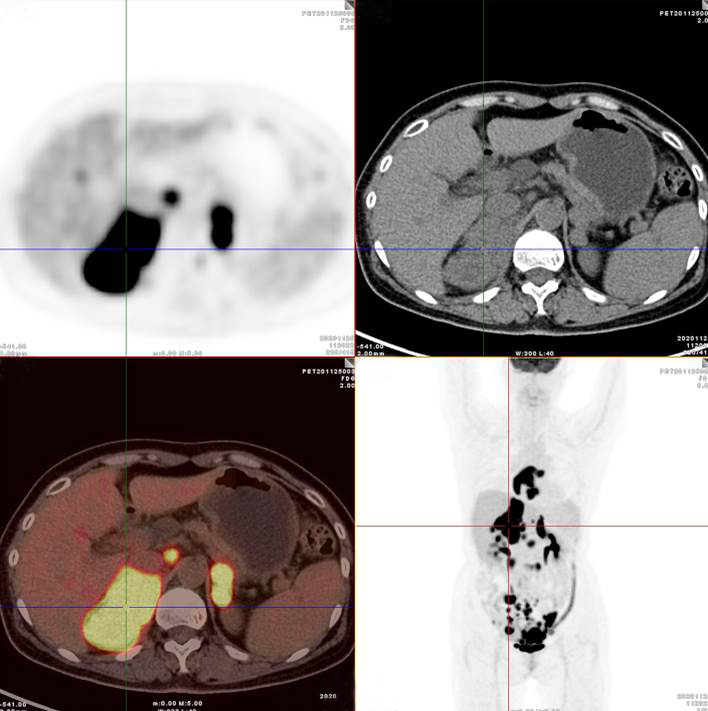

PET/CT影像圖

雙側(cè)腎上腺病灶、腹膜后淋巴結(jié)放射性攝取明顯增高

膽囊及雙腎上腺病灶、腹膜后淋巴結(jié)放射性攝取明顯增高